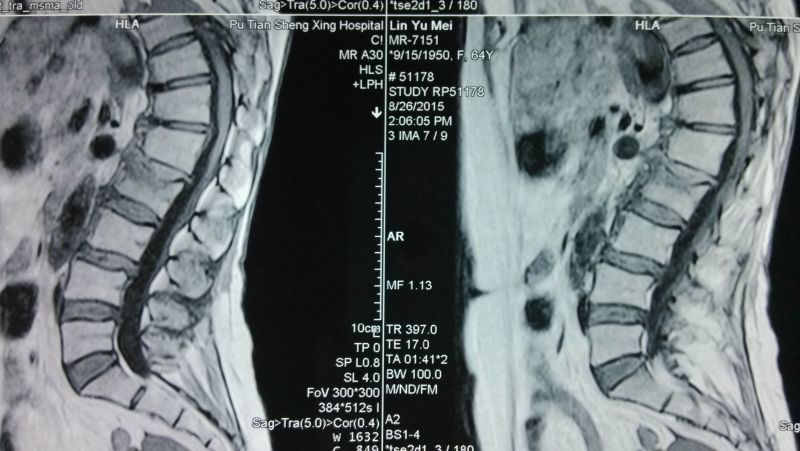

術(shù)前MRI(1)